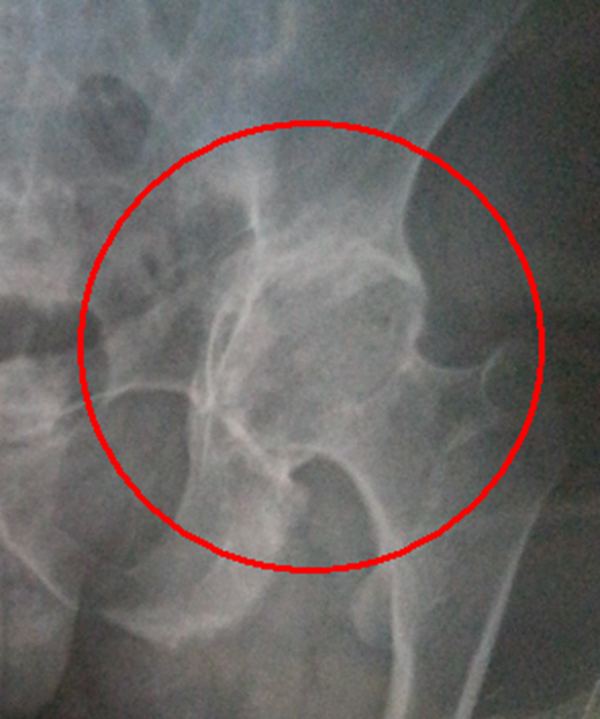

查瞅:厚皮性骨膜病的X线查瞅瞅来胫骨、腓骨、桡骨、尺骨等部位有增素性骨膜炎、充溢性骨膜增厚。

诊疗:依据皮肤及骨骼X线查瞅睹增素性骨膜炎、充溢性骨膜增厚的典范临床转变可作出诊疗。